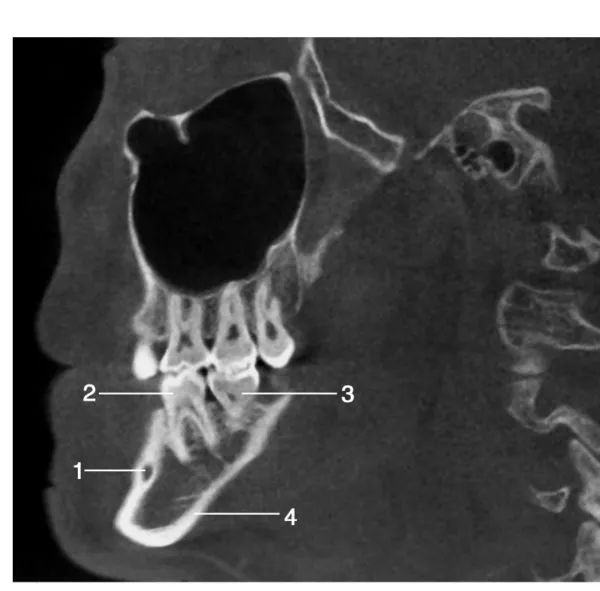

经下颌第一磨牙处层面矢状位图像

1.颏孔 ; 2.下颌第一磨牙 ; 3.下颌第二磨牙;4.下颌下缘